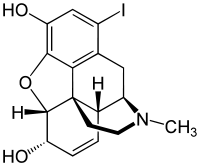

Several semi-synthetic opioids were developed in Germany in the 1910s. The first, oxymorphone, was synthesized from thebaine, an opioid alkaloid in opium poppies, in 1914.[228] Next, Martin Freund and Edmund Speyer developed oxycodone, also from thebaine, at the University of Frankfurt in 1916.[229] In 1920, hydrocodone was prepared by Carl Mannich and Helene Löwenheim, deriving it from codeine. In 1924, hydromorphone was synthesized by adding hydrogen to morphine. Etorphine was synthesized in 1960, from the oripavine in opium poppy straw. Buprenorphine was discovered in 1972.[228]